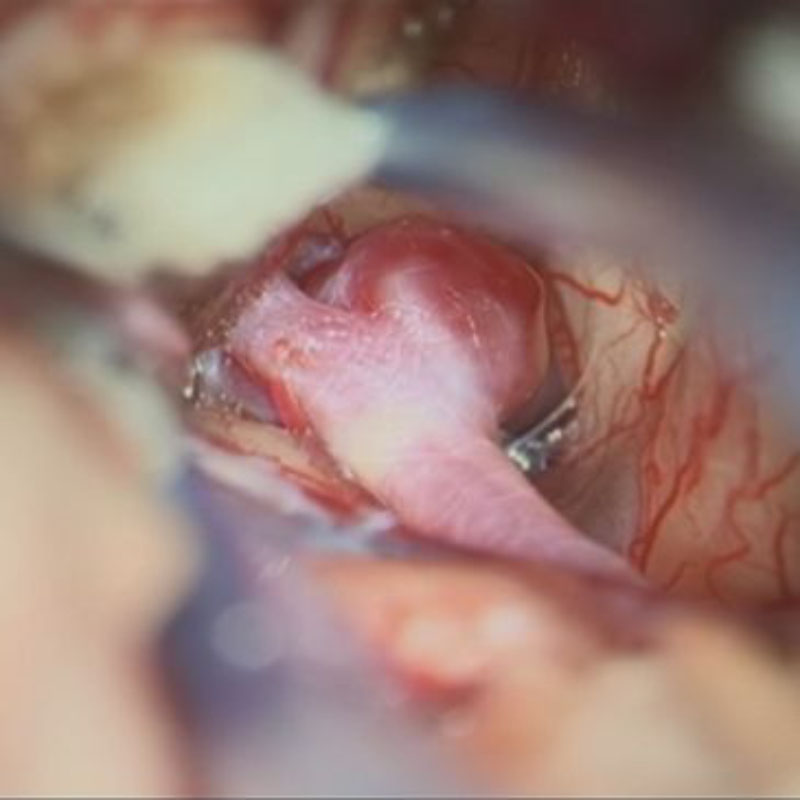

手術前

クリップ前

クリップ後

手術後